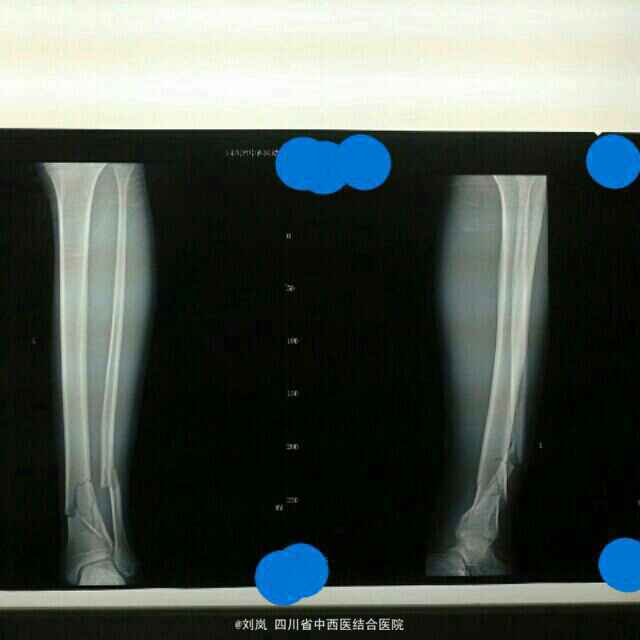

查体:形体消瘦,贫血貌,左小腿下端及左踝部肿胀、畸形改变,局部压痛明显,以左小腿下端及左踝关节为甚,可触及骨擦感及异常活动,左下肢及左踝关节功能活动障碍,无法自主站立及负重行走,左下肢纵向叩击痛(++);左膝关节活动正常;患肢末梢血循、活动及感觉正常;余肢体关节未见明显异常。 辅助检查: X线片示:左胫腓骨下段粉碎性骨折,骨折波及踝关节,骨折端错位明显,对位对线欠佳,左踝关节结构存

诊断: 1、左胫腓骨下段粉碎性骨折(波及踝关节) 2、营养不良 3、小细胞低色素贫血(原因不明) 4、低蛋白血症 5、脾大 治疗:患者入院后予行"骨折手法整复石膏外固定"制动,复查DR显示:折对位对线良好。向患者及家属说明病情,告知可保守及手术治疗,患者及家属选择手术治疗。故予完善相关术前检查及术前准备,术前输红细胞悬液1.5U及血浆150ml纠正贫血及低蛋白血症,在"全身麻醉"下行了"左胫骨远端骨折闭合复位经皮插入钢板内固定术+左腓骨中下段骨折切开复位钢板螺丝钉内固定术"。术后药物预防感染、消肿、止痛、止血,指导患者行患肢肌力及关节主动功能锻炼等治疗处理。术后2周患肢关节功能活动基本恢复正常,住院3周出院,手术效果理想。